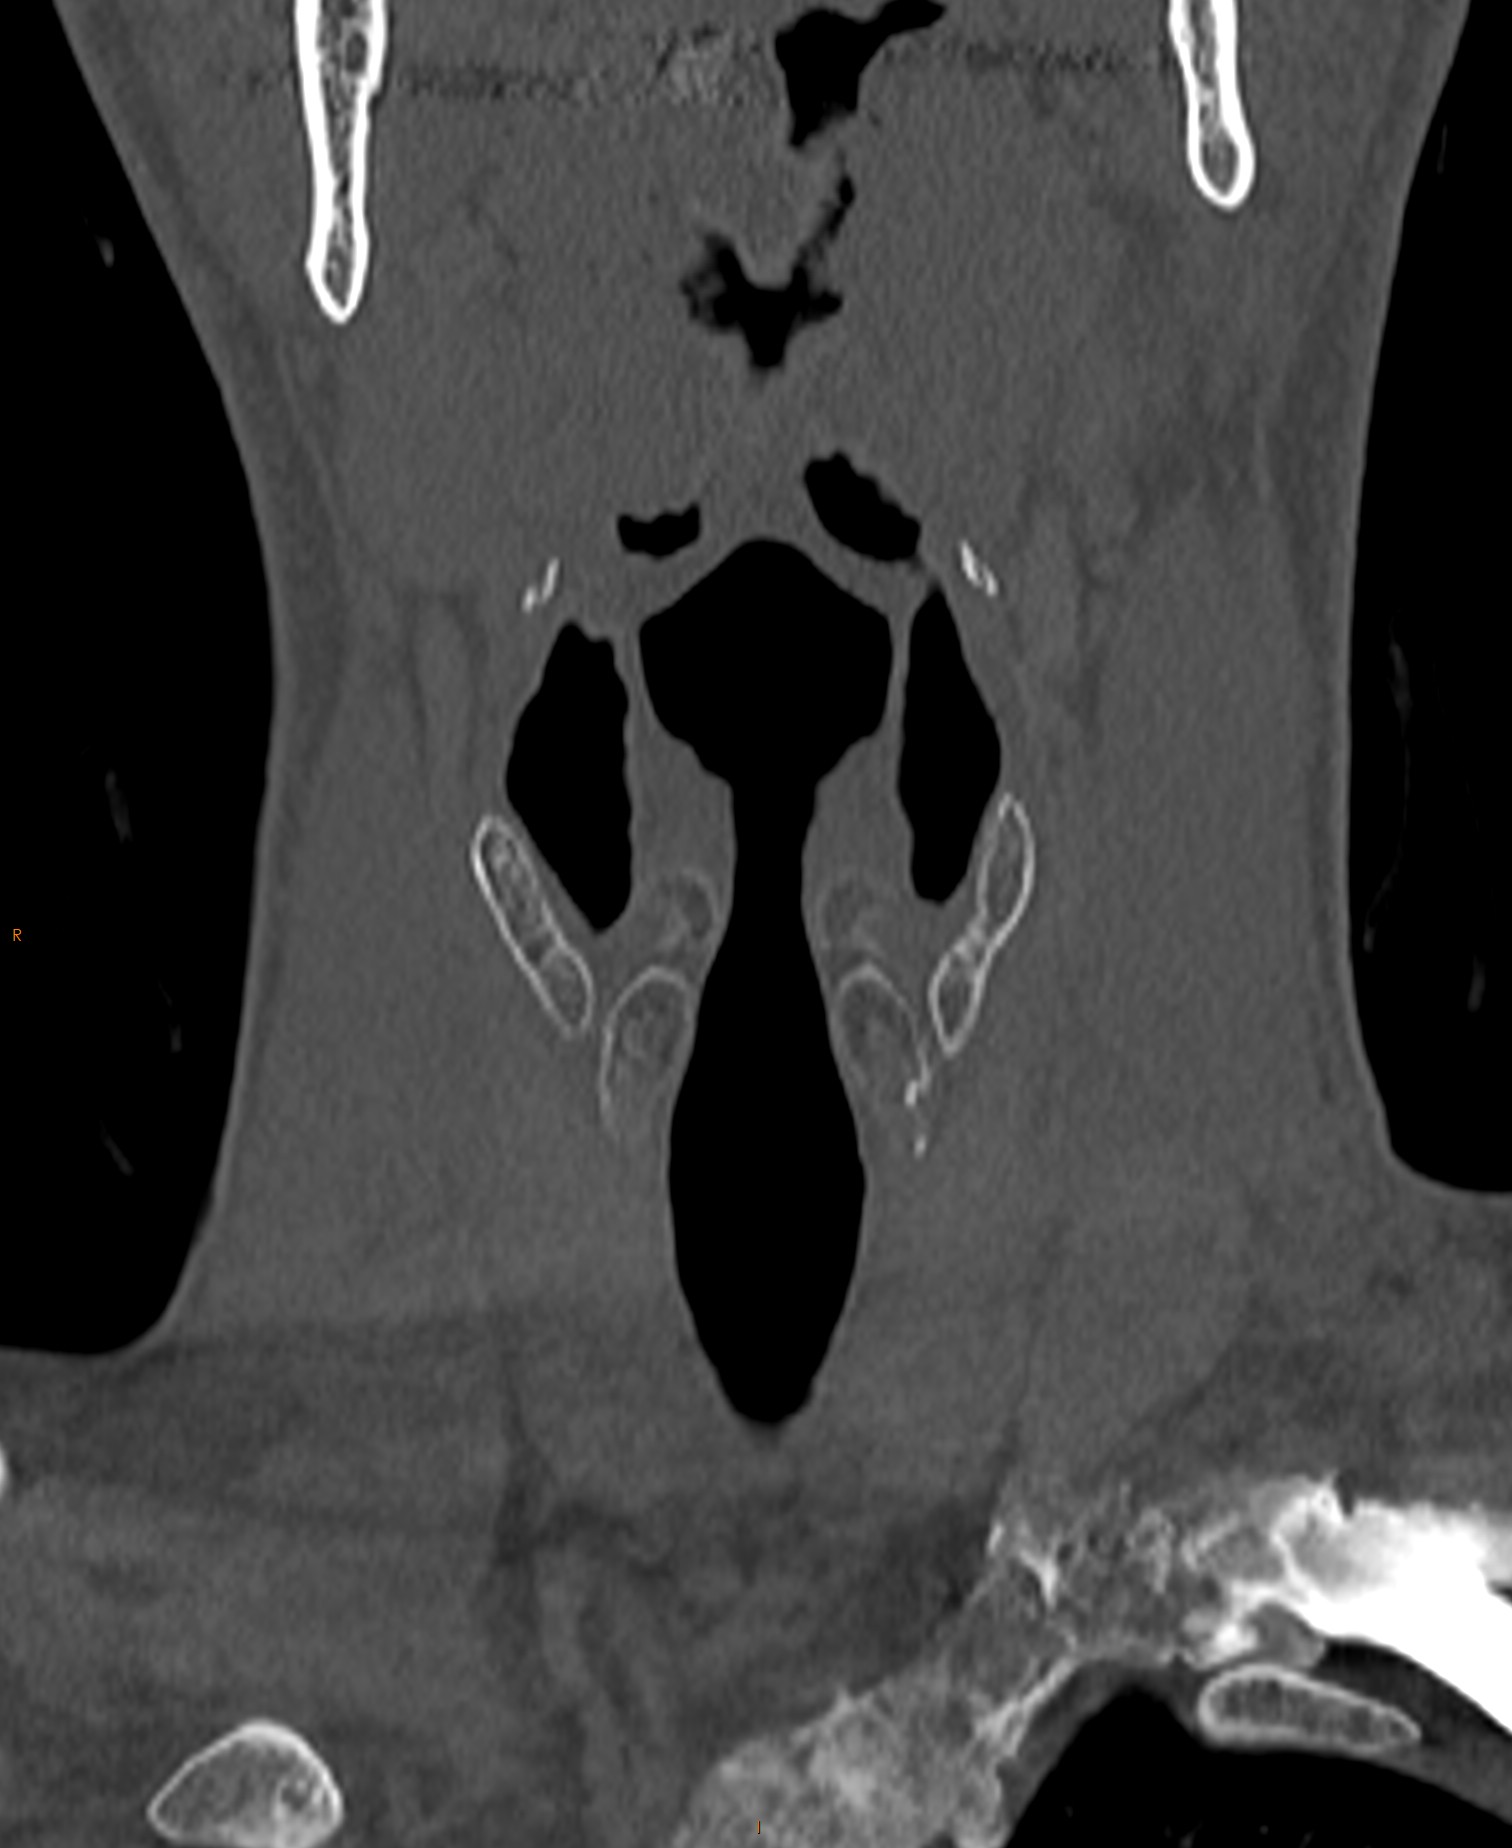

Normal CT neck Image

Normal neck (CT) Image Ct Neck With Contrast Radiopaedia The ct neck protocol serves as a radiological examination of the head and neck. With few exceptions, neck ct should be performed with intravenous contrast material, which accentuates abnormally enhancing. With few exceptions, neck ct should be performed with intravenous contrast material, which accentuates abnormally enhancing. Scrollable ct highlighted the anatomy of the neck. A normal ct scan of the. Ct Neck With Contrast Radiopaedia.